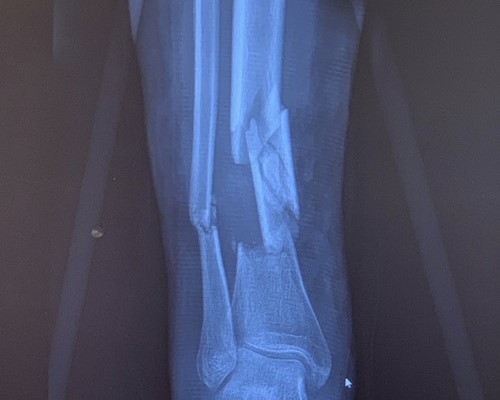

Leg Fracture